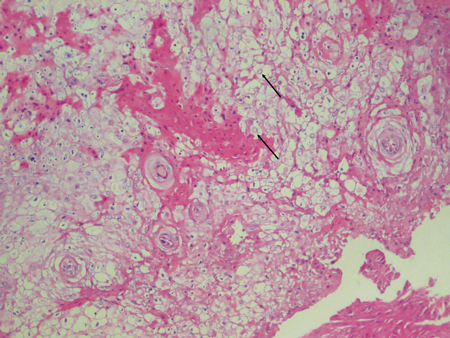

Quando visto microscopicamente, o tecido apresenta acantose ou um espessamento pesado da camada de células pickle do epitélio. Isto promove a aparência branca espessa que é muito característica do WSN. Outra característica observada é a limpeza citoplasmática das células epiteliais que um patologista reconhecerá.

-Nevo Esponja Branco. Cortesia de Doron Aframian, DMD, PhD.